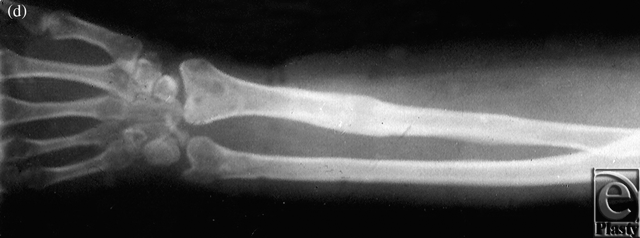

The patient was an 8-year-old boy who suffered from congenital pseudarthrosis forearm type II on both the radius and the ulna. After resection and Ilizarov external fixation/traction, the discrepant 8-cm-long space between the 2 sides was repaired. A secondary free fibula osteoseptocutaneous flap was then harvested from the contralateral side and transferred to the affected side to cover the tissue defects (Figs 1a-1e).

| Figure 1. Case 1: Congenital pseudarthrosis forearm. (a) Preoperative view, (b) Preoperative x-ray, (c) External fixation, (d) The 1-year postoperative view, and (e) A 1-year postoperative x-ray. |